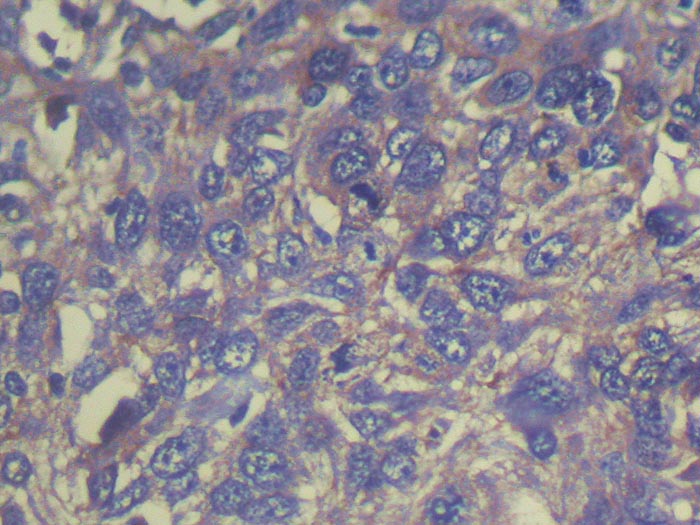

Immunohistochemistry of paraffin-embedded Human esophagus cancer tissue using TA365065 (THAP6 Antibody) at dilution 1/25 (Original magnification: x200)